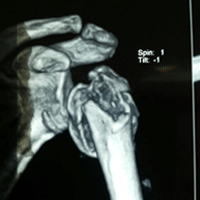

Case:21 Closed fracture of the neck of humerus with dislocation of Right shoulder

A female patient, aged 82 years had been diagnosed to have Closed fracture of the neck of humerus with dislocation of Right shoulder. She was treated operatively with Reduction & Internal fixation.

Pre-Operative

Post-Operative Ap View

Post-Operative Lateral View